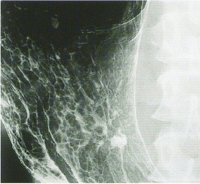

内視鏡では一見、胃潰瘍のように見えるが…

X線検査では潰瘍周囲に強い凹凸がみられ、

間違いなく癌であるとわかる。